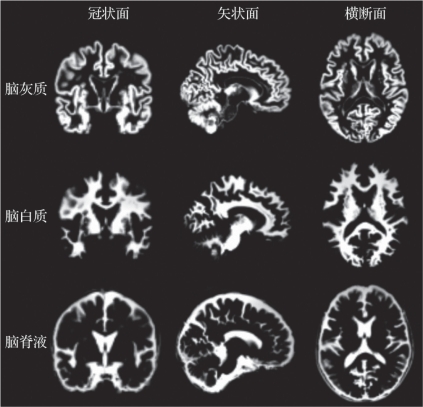

(3)脑组织分割:SPM软件对于经过标准化的个体脑图像,按照每种成分的不同,灰度值将脑组织分割成灰质图、白质图和脑脊液图(图5.16),VBM方法主要是对每个体素的灰质图和白质图进行浓度与体积的定量分析。(https://www.daowen.com)

图5.16 脑组织分割